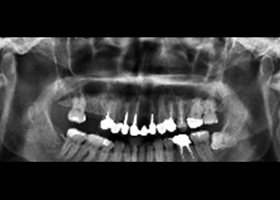

治療前,全口X光片。

治療後,全口X光片。